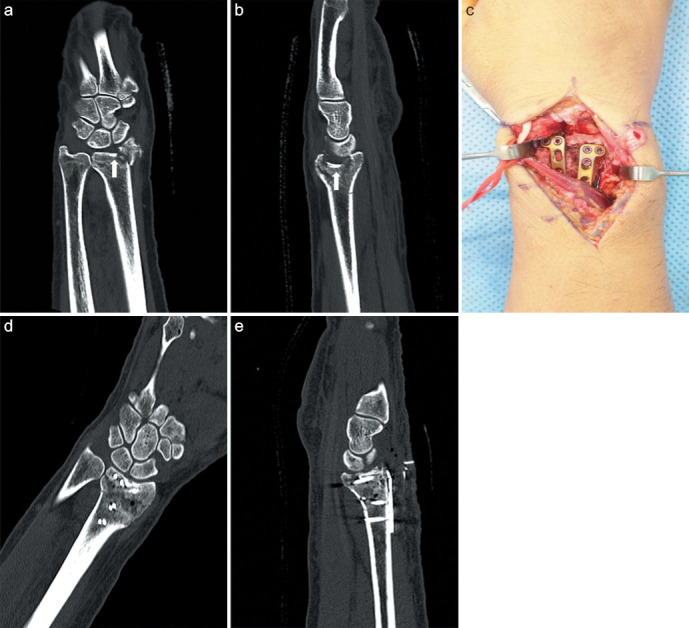

Methods: Thirty patients who underwent dorsal plating (Group A) (14 females, 16 males; mean age = 56.8 ± 10.1 years) and 28 who underwent volar plating with limited dorsal open reduction (Group B) (12 females, 16 males; mean age = 55.6 ± 17.7 years) for type C3 distal radius fractures with impacted articular fragments between 2006 and 2019 were retrospectively analyzed. The mean follow-up was 14.5 ± 3.2 months in group A and 13.2 ± 2.4 months in group B. The articular step-off, articular gap and joint penetration by screws on the computed tomography scans were used for radiologic evaluation. The functional outcomes were evaluated with range of motion, grip power, Quick Disabilities of the Arm, Shoulder, and Hand (DASH) score, and Mayo wrist score.

Results: No significant difference was found in the step-off distance at 1 year after surgery between the two groups (P < 0.05). The ranges of extension, rotation, and radial and ulnar deviations did not differ between the groups. However, group B had a significantly higher range of flexion in the wrist joint than Group A (P = 0.010). The grip power, DASH score, and Mayo wrist score did not also differ between the groups. Implant removal owing to any discomfort at the operative site was performed in 15 patients (63%) in Group A and 7 patients (28%) in Group B.

Conclusion: Similar clinical results can be obtained by both dorsal plating and volar plating with limited dorsal open reduction in treating type C3 distal radius fractures with impacted articular fragments. However, volar plating with limited dorsal open reduction can provide better wrist flexion with a low incidence of complications associated with implantation.